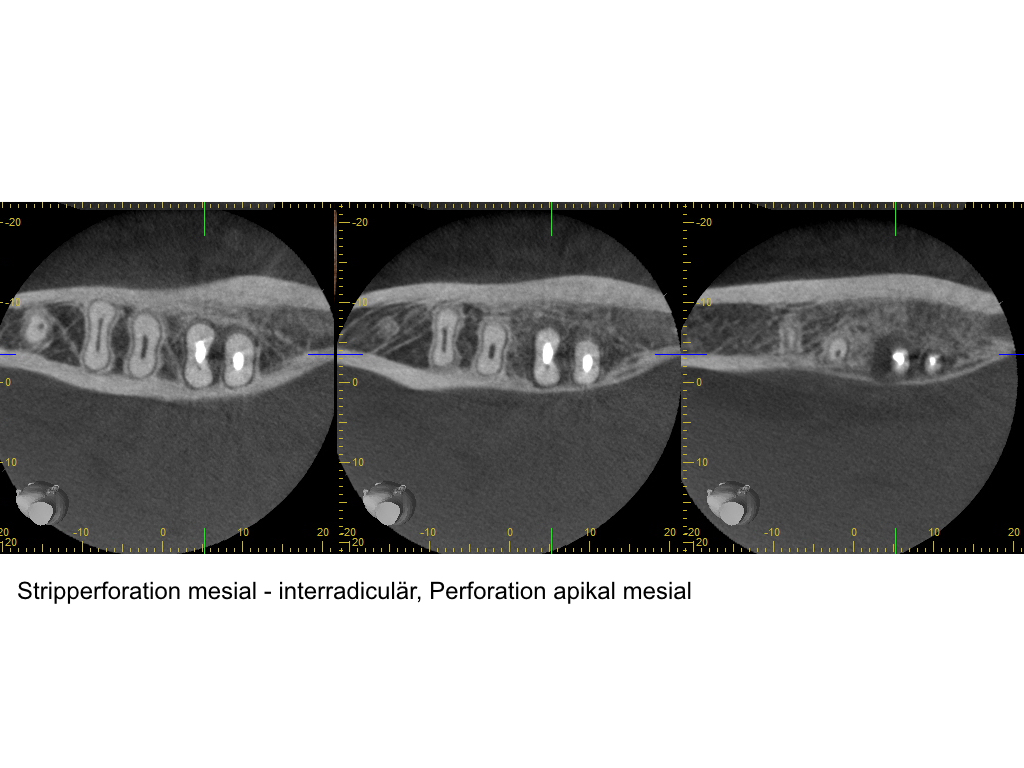

WS_Fallvorstellung11_2_16.003 Veröffentlicht 9. Februar 2016 am 1024 × 768 in Kofferdam – die einfachste Lösung